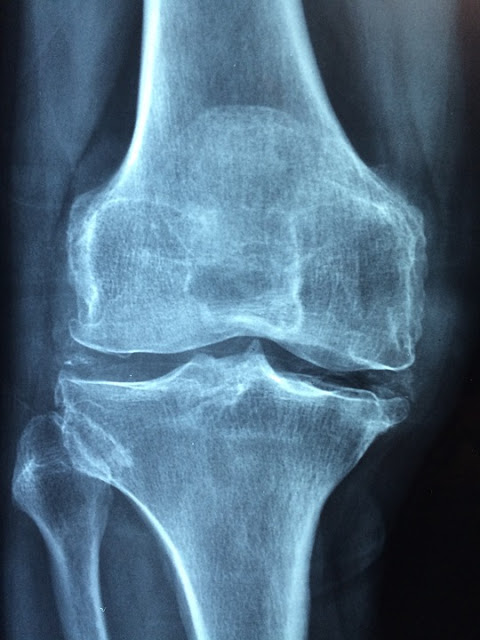

Osteoporosis disebabkan oleh menurunnya tingkat kepadatan tulang, dan bisa jadi disebabkan oleh bertambahnya usia. osteoporosis terjadi pada semua orang, namun ada beberapa orang yang lebih berisiko dan lebih cepat mengalami kondisi ini bila dibandingkan dengan orang lain. Saat muda, tulang manusia beregenerasi dengan cepat serta berada dalam kondisi padat dan kuat. Namun seiring bertambahnya usia, tulang lama tidak segera tergantikan dengan tulang baru dan tidak lagi bertumbuh. Hal ini membuat tulang secara perlahan menjadi lebih rapuh. Sehingga kepadatan tulang menjadi semakin berkurang dan menjadi lemah, keropos, dan lebih rentan retak.

Osteoporosis dapat disebabkan oleh banyak faktor, dan faktor tersebut juga dapat dipengaruhi oleh jenis kelamin. Pada wanita, hormon estrogen dibutuhkan untuk menjaga kesehatan tulang. Namun yang terjadi setelah menopause adalah penurunan kadar estrogen dalam tubuh yang turut mengakibatkan penurunan kepadatan tulang secara drastis. Dan jika kadar testosteron pada pria rendah, maka hal tersebut dapat mengakibatkan risiko osteoporosis yang meningkat. Selain itu, osteoporosis juga dapat disebabkan bila Anda mengonsumsi minuman keras berlebihan dan mengonsumsi obat-obatan seperti glukokortikoid atau obat-obatan steroid selama lebih dari tiga bulan.